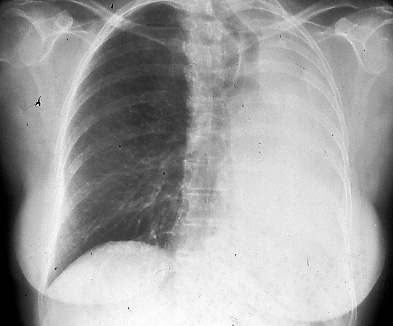

Fig. 14a and 14b: Posterior-anterior and lateral chest radiographs showing total collapse of left lung due to a central bronchogenic carcinoma, T3.